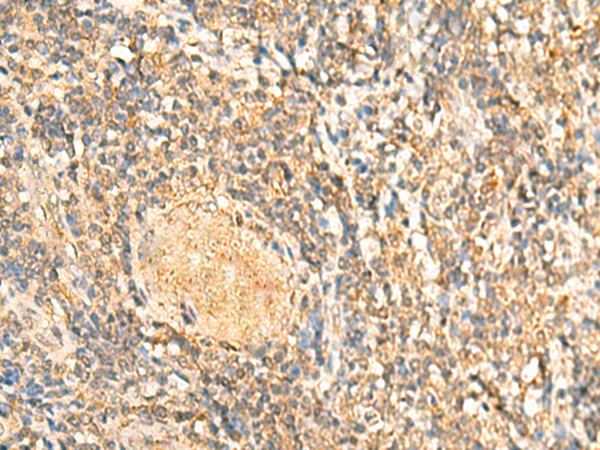

分类: 科研抗体货号: P10047别名: RAB1; YPT1应用: IHC反应种属: Human, Mouse, Rat